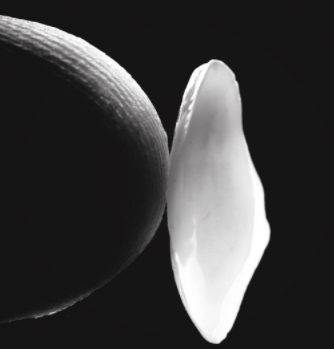

Il trattamento del canale consiste nella rimozione del tessuto nervoso vascolare (del “nervo”) dai canali radicolari, seguito dalla pulizia, dall’ampliamento e dalla sterilizzazione di questi canali e quindi dalla loro ostruzione. L’otturazione del canale rappresenta l’ultimo stadio del trattamento endodontico e consiste nel sigillare le radici con materiali speciali, che prevengono le infezioni.

Il dente ha un tessuto vascolare e nervoso (nervo) all’interno dei canali radicolari, che garantisce l’apporto di nutrienti. Quando si verificano infiammazioni o infezioni di questo tessuto, è necessario rimuoverlo. Il trattamento del canale consiste nel rimuovere il nervo dai canali radicolari, seguito dal riempimento (riempimento) con materiali speciali, che assicurano la tenuta e prevengono le infezioni. Inizialmente, questo trattamento viene eseguito per rimuovere il dolore e curare o prevenire l’infezione. L’obiettivo finale è quello di mantenere la funzionalità del dente.